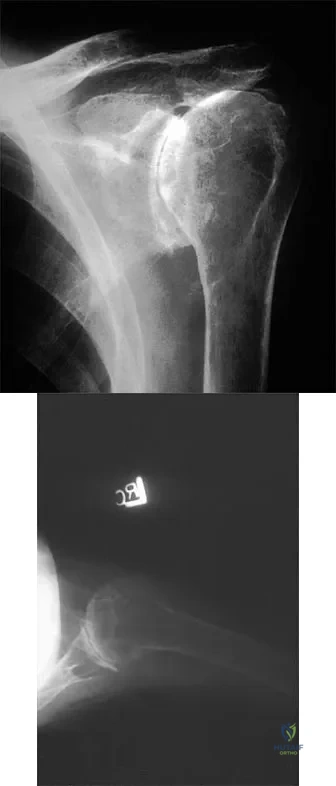

A 12-year-old boy falls from a bicycle. A radiograph of his injured shoulder is shown in Figure 41. What is the optimal method of treatment?

The radiograph reveals a distal clavicle fracture. In children, a periosteal sleeve will remain attached to the intact coracoclavicular ligament, and as such, remodeling can be expected. Therefore, nonsurgical management with a sling is preferred. Surgical treatment is not necessary, and a shoulder spica cast offers no advantage over a simple sling.

A 55-year-old woman with polyarticular rheumatoid arthritis has had progressively increasing left shoulder pain for the past 2 years despite nonsurgical management. No focal weakness is noted during examination of the shoulder. AP and axillary radiographs are shown in Figures 47a and 47b. Treatment should consist of

Unconstrained total shoulder arthroplasty has been found to yield satisfactory results in a high percentage of patients with rheumatoid involvement of the glenohumeral joint. Pain relief has been more predictable with total shoulder arthroplasty than humeral arthroplasty, and a glenoid component is favored when there is sufficient glenoid bone stock and an intact rotator cuff. Constrained or fixed-fulcrum devices have an unacceptably high failure rate because of loosening. Glenohumeral arthrodesis is avoided when the deltoid or rotator cuff is functioning because the functional results after arthroplasty are superior when compared with results of arthrodesis. Arthroscopic synovectomy may be helpful in early stages of the disease before extensive cartilage damage has occurred. Boyd AD Jr, Thomas WH, Scott RD, Sledge CB, Thornhill TS: Total shoulder arthroplasty versus hemiarthroplasty: Indications for glenoid resurfacing. J Arthroplasty 1990;5:329-336.